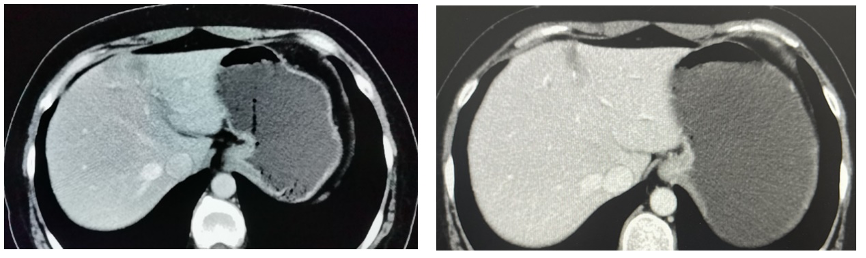

⑤一线治疗:给予GP方案(吉西他滨+顺铂)化疗6周期,左肺胸膜下病变无变化。肝转移灶部分较前增大(图2)。

图2. 肝最大病灶直径1.2 cm(2017年12月,左图),肝最大病灶直径3.8 cm(2018年6月,右图)